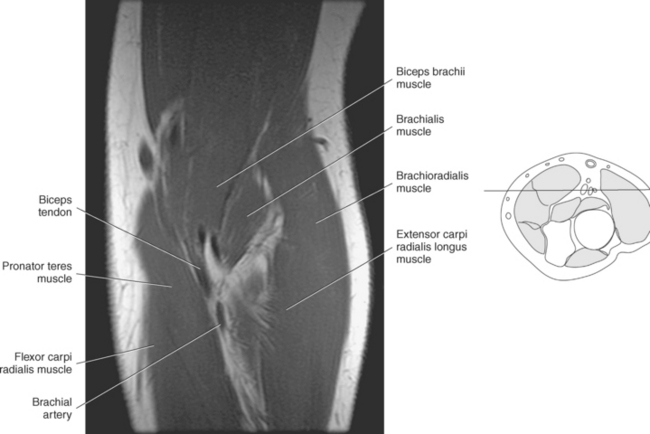

The elbow is a complex hinge-pivot joint created by the articulations of the humerus, radius, and ulna. All three articulations communicate with each other within a single joint capsule. The radius and ulna are the bones of the forearm, with the radius located on the lateral side. The radioulnar and radiohumeral articulations create the pivot joint that aids in supination and pronation of the elbow. The radiohumeral and ulnohumeral articulations form the hinge joint that allows for flexion and extension (Figures 9.70 through 9.73).

The distal portion of the humerus has two distinct prominences termed the medial and lateral condyles, with associated epicondyles, that provide attachment sites for tendons and ligaments (Figure 9.70). The medial epicondyle serves as the site of origin for the common flexor tendon, pronator teres muscle, and medial collateral ligament, whereas the lateral epicondyle serves as the attachment site for the common extensor tendon, supinator muscle, and lateral collateral ligament. Just lateral to the medial epicondyle along its posterior surface is a shallow groove containing the ulnar nerve. Two depressions located on the distal humerus are the anterior coronoid fossa and the deep posterior olecranon fossa. These depressions accommodate the coronoid and olecranon processes of the proximal ulna (Figures 9.70, 9.71, and 9.73). The distal humerus has two cartilage-covered articular surfaces—the capitellum and the trochlea for articulation with the radius and ulna (Figure 9.71). The lateral of the two surfaces is the capitellum, a rounded projection that articulates with the concave surface of the radial head. The trochlea is more medial and has the appearance of an hourglass if viewed in the horizontal plane. The shape of the trochlea helps keep the ulna in position during flexion between the distal humerus and proximal radius (Figure 9.73).

The radius is a long, slender bone with a proximal portion that consists of the radial head, neck, and tuberosity. The radial head has a flat cartilage-covered depression or fossa (fovea of the radius) that articulates with the capitellum of the humerus. In addition, the articular circumference of the radial head articulates against the radial notch of the ulna during supination and pronation. The radial head is attached to the body of the radius by the narrow radial neck. Located at the distal portion of the neck on the medial side of the radius is a roughened projection termed the radial tuberosity. The radial tuberosity serves as the attachment point for the biceps brachii muscle (Figures 9.72 through 9.74).

The ulna is located medial within the forearm. The proximal ulna consists of the olecranon and coronoid processes and the trochlear and radial notches. The superficial dorsal surface is formed by the hook-shaped olecranon process, which is the attachment site for the triceps brachii. The trochlear notch is a half-moon-shaped concave articular surface that curves around the trochlea of the humerus. This articulation allows for flexion and extension of the elbow. Located on the anterior portion of the distal end of the trochlear notch is a small beaklike process called the coronoid process. Just distal and lateral to the coronoid process is a flattened depression called the radial notch. It is covered by articular cartilage for articulation with the radial head. Immediately distal to the coronoid process is a roughened bony surface termed the ulnar tuberosity. The tendon of the brachialis muscle inserts on both the coronoid process and the ulnar tuberosity (Figures 9.72, 9.73, 9.75, and 9.76).

The entire elbow joint is surrounded by a relatively loose joint capsule that allows for the movements of flexion and extension. The joint capsule is weaker anteriorly and posteriorly but is reinforced medially and laterally by the strong radial and ulnar collateral ligaments (discussed in the next section). Located within the olecranon and coronoid fossas are fat pads that fill the space between the synovial membrane and joint capsule (Figures 9.77 and 9.78). The fat pads help cushion the area where the olecranon and coronoid processes move during flexion and extension of the elbow. There are two clinically important bursae located in the elbow: the olecranon bursa and the distal bicipitoradial bursa. The olecranon bursa is located within the subcutaneous tissue overlying the olecranon process (Figure 9.77). The distal bicipitoradial bursa lies between the insertion of the biceps tendon and the humerus.

The stability of the elbow joint primarily depends on the collateral ligaments that are woven into the lateral portions of the joint capsule. The ulnar collateral ligament (medial collateral ligament) consists of three components: an anterior band, a posterior band, and a transverse band (ligament of Cooper) (Figures 9.79 through 9.82). The anterior band, which is the strongest, extends from the medial epicondyle of the humerus to the medial aspect of the coronoid process. The posterior band originates along with the anterior band from the medial epicondyle of the humerus and inserts on the medial aspect of the olecranon process, forming a triangular plate. The weaker transverse band stretches between the medial surfaces of the coronoid and olecranon processes to unite the anterior and posterior bands. Reinforcing the lateral side is the triangular radial collateral ligament (lateral collateral ligament). The radial collateral ligament originates from the lateral epicondyle of the humerus, adjacent to and beneath the common extensor tendons, and spreads distally to insert on the annular ligament and the anterior and posterior margins of the radial notch of the ulna (Figures 9.81 and 9.83). The annular ligament forms a fibrous ring that encircles the radial head, with a narrow portion that tightens around the radial neck to prevent inferior displacement of the radius (Figures 9.79 and 9.83 through 9.85). The annular ligament is considered a key structure in the proximal radioulnar joint, allowing the head of the radius to rotate freely. Just distal to the annular ligament is the quadrate ligament, a small band of tissue that passes from the radial notch of the ulna to the neck of the radius to provide stability to the joint during supination and pronation.

The pronator teres muscle has two heads of origin. Its humeral head originates from the common flexor tendon, whereas the ulnar head originates near the coronoid process of the ulna. The pronator teres muscle courses obliquely before inserting on the lateral surface of the radius at midshaft. It works in conjunction with the pronator quadratus muscle to pronate the forearm (Figure 9.86).

The flexor carpi radialis muscle originates from the common flexor tendon and is located medial to the pronator teres. Its tendon passes through the carpal tunnel before inserting on the palmar surface of the base of the second metacarpal. Its actions include flexion and radial deviation of the hand at the wrist joint (Figure 9.86).

The muscles of the superficial dorsal group are demonstrated in Figures 9.87 through 9.98 and 9.100. The brachioradialis is an extensor muscle lying along the lateral border of the forearm. This large muscle arises from the upper two thirds of the supracondylar ridge of the humerus and attaches distally to the radial styloid process. The brachioradialis flexes the forearm at the elbow and assists with pronation and supination (Figure 9.100).

The extensor carpi radialis longus muscle arises just distal to the brachioradialis on the lower third of the supracondylar ridge of the humerus. It runs posterior and deep to the brachioradialis to insert on the base of the second metacarpal. It acts as an extensor and abductor of the hand at the wrist joint (Figure 9.100).

The primary arteries supplying the shoulder region include the axillary and brachial arteries (Figures 9.34 through 9.45 and 9.144, A). The axillary artery begins at the lateral border of the first rib as a continuation of the subclavian artery. It ends at the inferior border of the teres major muscle, where it passes into the arm and becomes the brachial artery. The axillary artery and its branches supply blood to numerous thoracic and shoulder structures, including the first and second intercostal spaces, axillary lymph nodes, mammary gland in women, and scapular, serratus anterior, pectoral, latissimus dorsi, deltoid, and triceps brachii muscles. The branches of the axillary artery typically include the superior thoracic, thoracoacromial, lateral thoracic, subscapular artery, and anterior and posterior humeral circumflex arteries. The brachial artery is the principal arterial supply to the arm. It courses inferiorly on the medial side of the humerus then continues anterior to the cubital fossa of the elbow. The brachial artery is relatively superficial and palpable throughout its course. It accompanies the median nerve, which crosses anterior to the artery in the middle of the arm. During its course, the brachial artery gives rise to numerous muscular branches, which include the profunda brachii, superior ulnar collateral, and inferior ulnar collateral arteries (Figure 9.144, A).

The brachial artery divides at the cubital fossa into the radial and ulnar arteries (Figure 9.144, A).